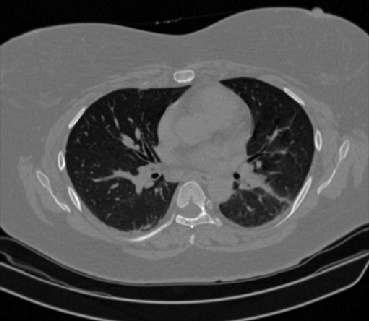

It should be mentioned that for explainability purposes [7, 8, 9], an anchor set was generated for the COV19-CT-DB database [5]. This included 11 anchors, each representing a respective 3-D CT scan obtained through an appropriate clustering procedure. Figure 2 shows a series of slices from a COVID-19 case, whereas Figure 3 shows a series of slices from a non COVID-19 case.